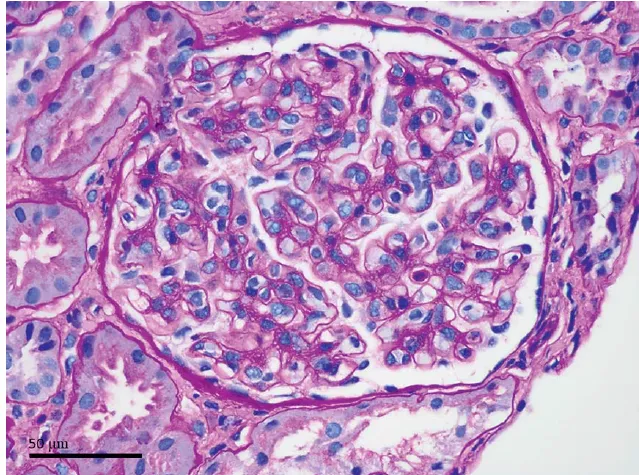

Proteinúria entre 0,5–1,0 g/dia na NIgA não é benigna e já se associa a maior risco de progressão renal. A evidência atual reforça <0,5 g/dia como alvo terapêutico, valorizando proteinúria cumulativa e tendência ao longo do tempo. Antes de pensar em imunossupressão, o foco deve ser otimização máxima da terapia de suporte e estratificação cuidadosa de risco.